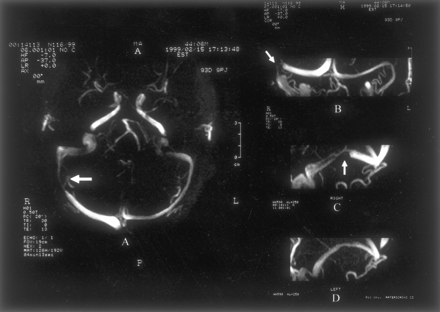

我们调查了111例正常脑脊液压力188金宝慱官网下载(60 - 192毫米范围H2O;意思是135;SD 33)。所有受试者正常的大脑直接上级矢状先生和鼻窦,盖伦的静脉,和内部脑静脉被认为在所有情况下,而枕窦是只有5%的病人。MRV显示正确,左,或共显性的TS在51%,18%,31%的病例。六十六例正常MRV (图1)而45主题显示干扰的一个或两个TS流。流的扰动分类为流动间隙如果缺乏信号流的长度小于或等于三分之一窦。在一个TS流差距观察静脉造影照片先生在29.7% (33/111);188金宝慱官网下载其中,36.4%(12/33)发生在占主导地位的TS。剩下的21例焦流缺口被认为在非惯用(42.4%,14/33)TS的窦或被认为是共显性的(21.2%,7/33)。流缺口位于近端部分TS在15%(5/33)的被试(图2),而流量差距mid-lateral部分TS中85%(28/33)的人(图3)。关于后个人,其中75%(21/28)有焦空白暗示蛛网膜颗粒的流动。缺乏信号流在一个整个TS在9%(10/111)的病例。188金宝慱官网下载值得注意的是,只有2个人(1.8%)焦TS流缺口。

值得注意的是流差距主要被发现在TS的mid-lateral部分85%的个体,而只有15%的情况下显示的近端部分TS流差距。因为蛛网膜颗粒通常发生在TS的mid-lateral部分,可以假设在某些个人突出蛛网膜颗粒(或血栓形成在这些解剖结构)可能产生相对腔妥协从而导致压力梯度或扰流。同意这个结果,一些作者10显示硬脑膜的鼻窦的小型或大型蛛网膜颗粒19 29尸体标本;这些发现的绝大多数在TS左侧优势和优惠的本地化mid-lateral窦的一部分。同意这个结果,增强对比度MRV或对比增强CT脑鼻窦的研究显示蛛网膜颗粒的发生在13%和24%的主题。10不同于差距发生在mid-lateral部分TS流,流缺口位于鼻窦的近端部分可能是由于近端发育不全的TS。最后,10 111例(9%)受试者缺乏流信号在整个TS。整个TS的发育不全可能解释这一发现。188金宝慱官网下载